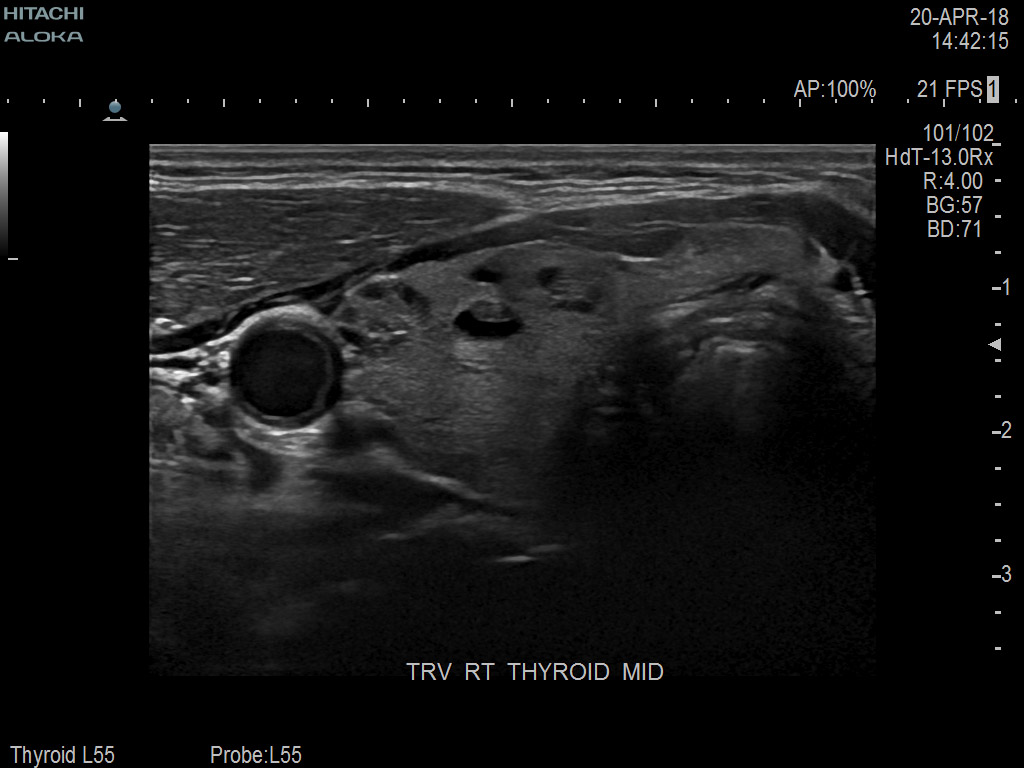

Superior guidance for all applications

Fujifilm Healthcare Americas is committed to designing tools that help surgeons navigate inside the human body and provide the necessary information to immediately make critical surgical decisions.

Fujifilm Healthcare's dedication to Surgeons provides outstanding ultrasound technology, professional support and the specialized tools necessary to best perform comprehensive real-time ultrasound imaging in Breast Surgery, General Surgery, Laparoscopic Surgery, Neurosurgery, Robotic Surgery and Surgical Oncology.